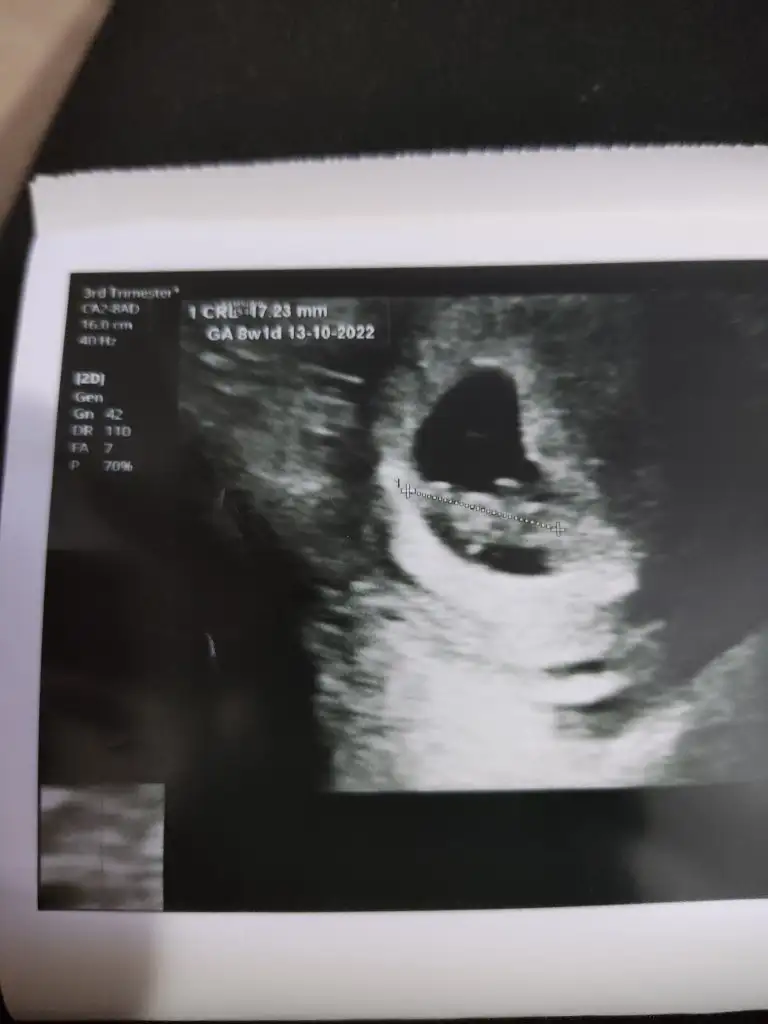

Kız gibi sankiİkra Hanım, 11+6 ultrason görüntümü paylaşıyorum yorumlayabilir misiniz?Ikra meyra

Kız gibi

Teşekkür ederim yorumunuz içinKız gibi sanki